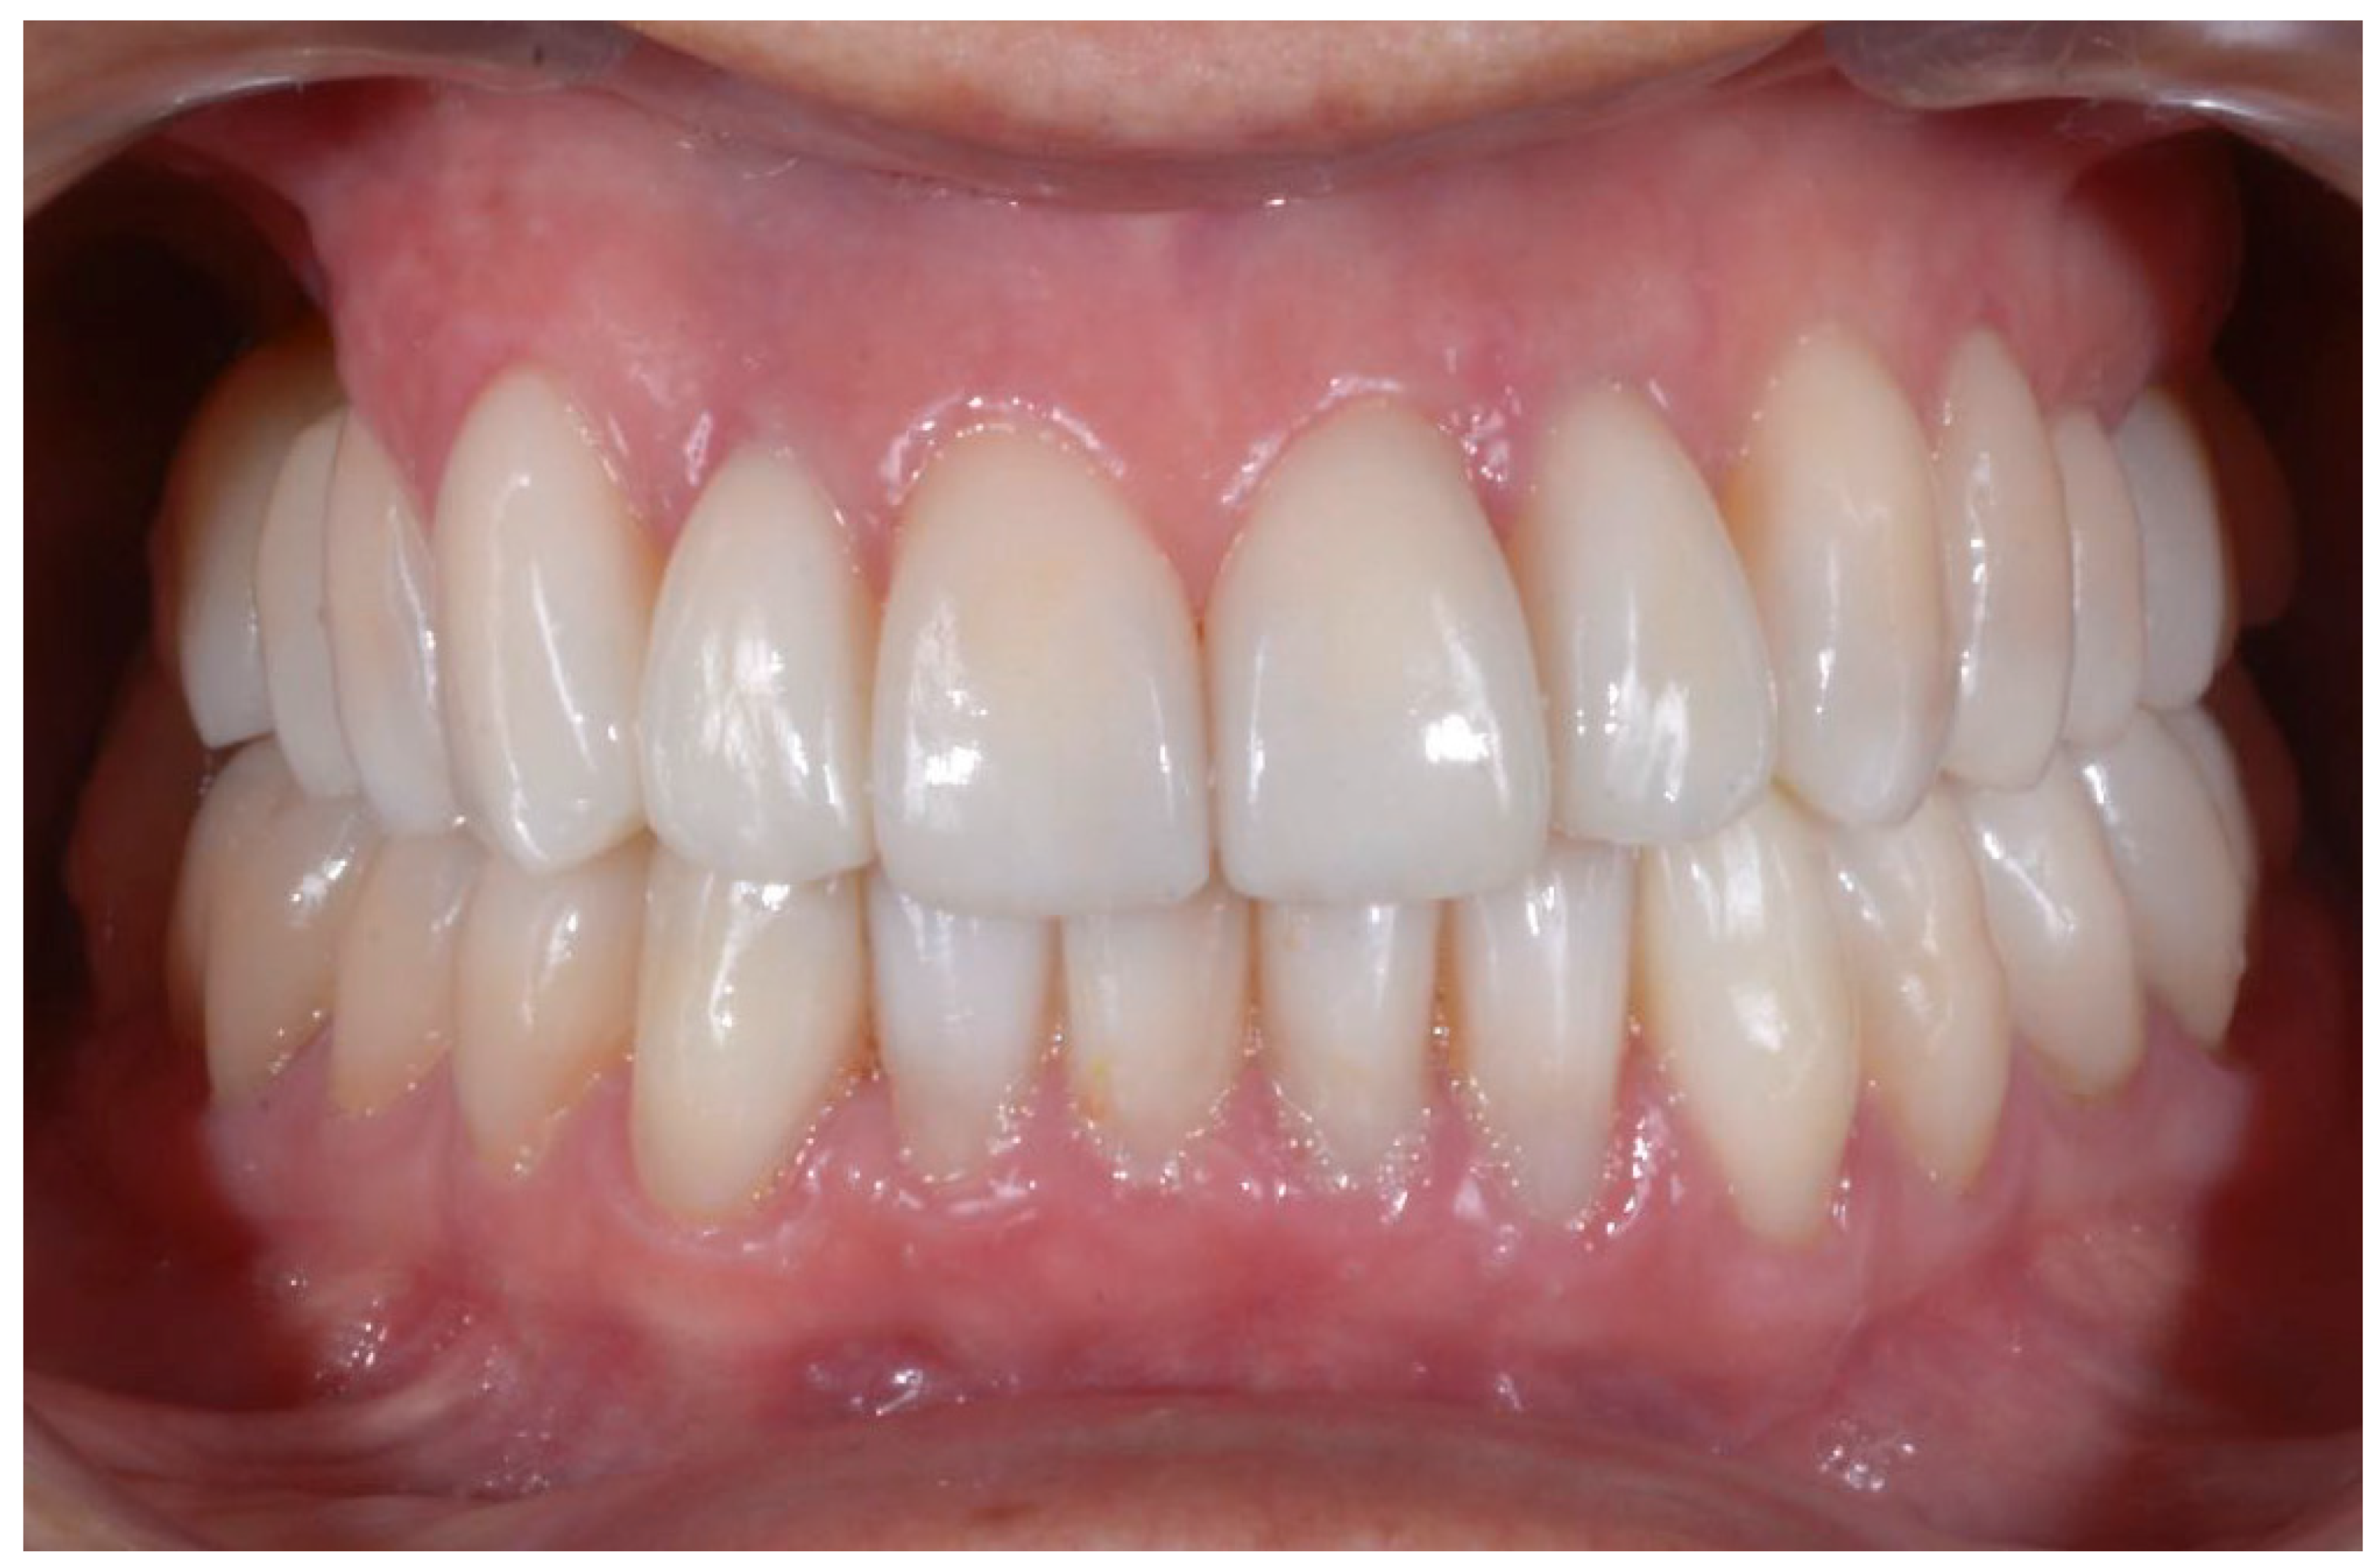

2.2. Clinical Example

2.3. Outcome Achieved